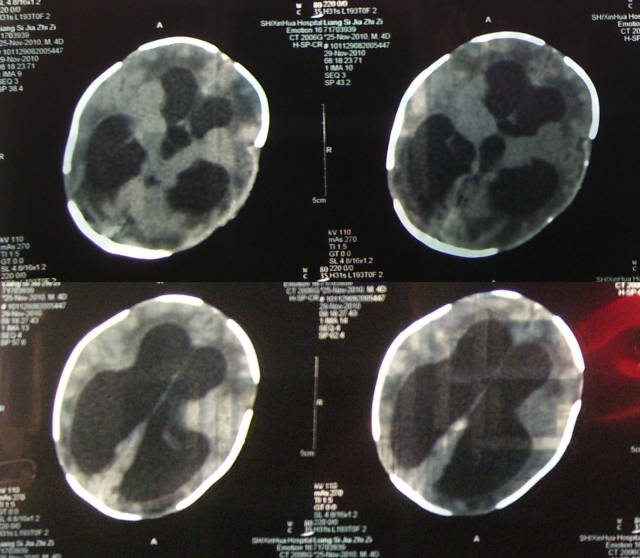

这是一个脑积水患儿的片子

图片尺寸640x557